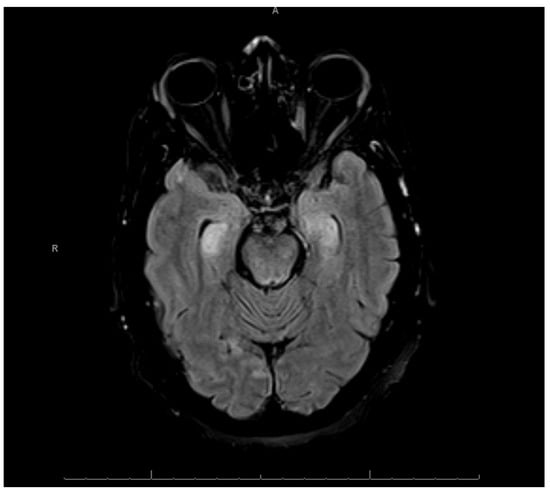

After managing the patient’s agitation, ceftriaxone and doxycycline were initiated to treat presumed community acquired pneumonia, antihypertensives were initiated to manage the patient’s marked hypertension, and intravenous thiamine was initiated prophylactically. Magnetic resonance imaging (MRI) of the brain was then completed, which demonstrated areas of restricted diffusion involving the bilateral hippocampi, thalami, putamen, and caudate nuclei (Figure 1, Figure 2, and Figure S1). This pattern was suspicious for cytotoxic edema resulting from hypoxic, ischemic, or toxic encephalopathy.

Figure 1. Lesions in Bilateral Hippocampi. Diffusion-weighted brain MRI showing restricted diffusion in bilateral hippocampal regions, as well as subtle restriction in the right occipital lobe.